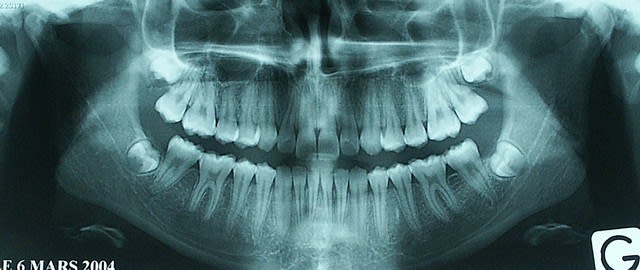

Compte rendu de l'IRM des ATM:

- protocole: séquences dynamiques en sagittales droite et gauche, et réalisation de séquences sagittales en T2.

- résultat: sur les séquences T2, il n'y a pas dépanchement intra-articulaire. Le ménisque gauche est correctement situé et sa mobilité est satisfaisante lors de l'ouverture de la bouche. A droite, il semble exister une désinsertion postérieure du ménisque qui se luxe antérieurement, particuliérement lors de l'ouverture de la bouche.

- Conclusion: la subluxation antérieure de la bouche ouverte se fait normalement: la ménisque gauche présente une cinétique normale, tandis que le ménisque droit semble présenter une luxation antérieure.

Les examens ont été prescrits par l'ortho. Je ne sais pas si l'IRM était indispensable pour confirmer le diagnostic d'antéposition discale.